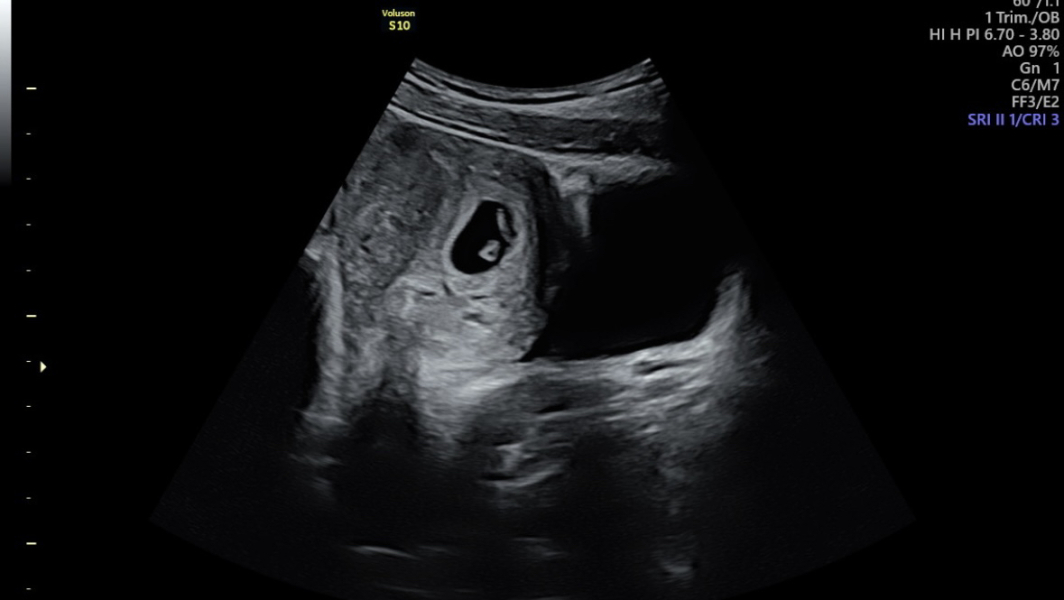

Runsandbuns · 02/12/2024 12:05

Morning all- little update- a healthy looking baby (if you can call it that at this stage) with a strong heart rate - measuring at 6 weeks 5 days 🤗 soo happy.

Hope yours goes well today @JDecember21- keep me updated ♥️

11DPO positive - but concerned

@Runsandbuns so pleased for you, lovely scan image and great you can see heartbeat!